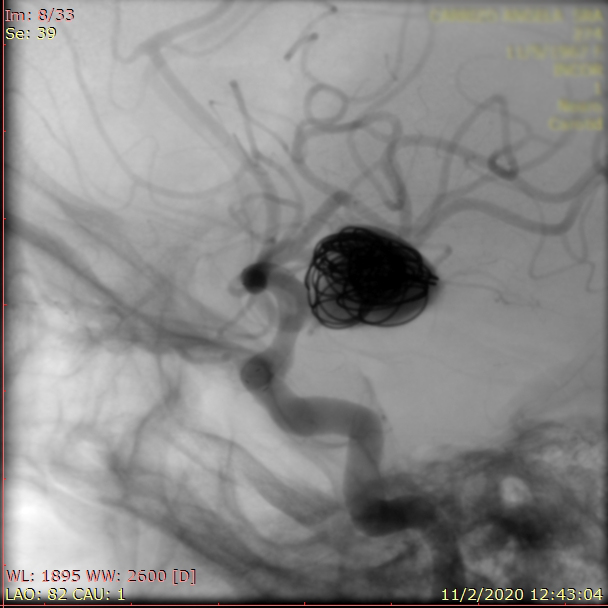

La paciente ingreso al Servicio de Hemodinamia el día martes 11 de febrero con un aneurisma cerebral gigante en la carótida izquierda y se le practicó una embolización; es decir una oclusión por dentro del mismo, donde se colocó un dispositivo denominado coils más un stent diversor de flujo. El procedimiento fue exitoso y contó con la colaboración de médicos neurointervencionistas del Instituto Oulton de la Ciudad de Córdoba.